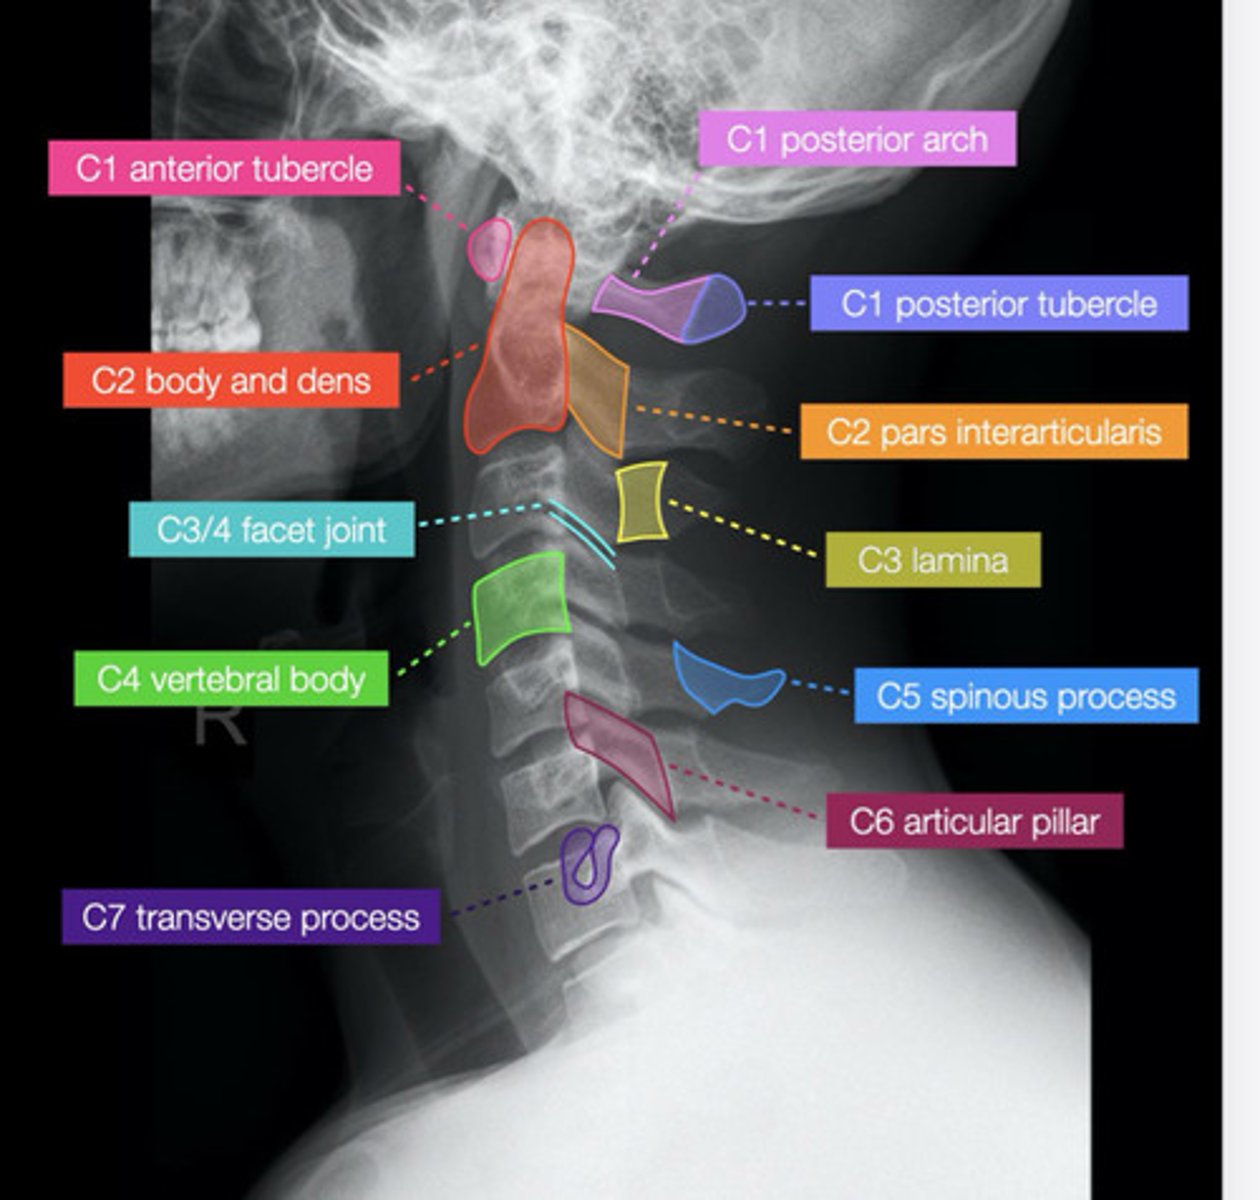

normal C/S

lateral spine xray